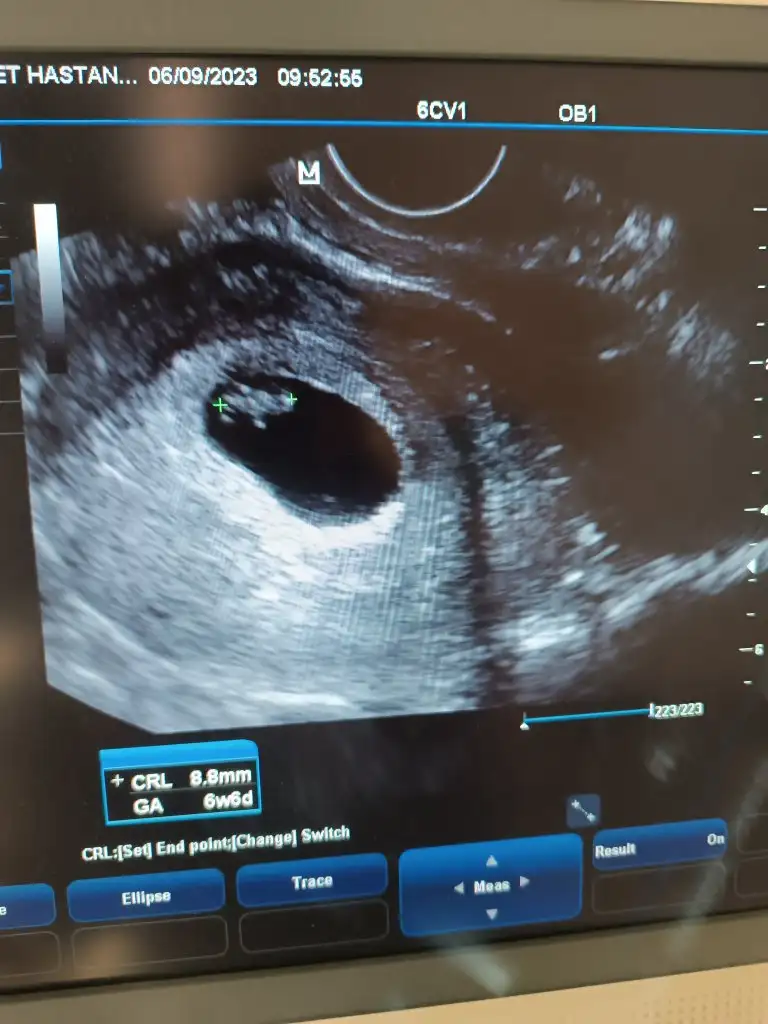

Bizi de tahmin edermisiniz 6+6 günlük vajinal usgÇok sevindim.

Hanımlar bana yorum yapınnAy bana da yorum yapar mısınız 6+4 ultrasonda karından